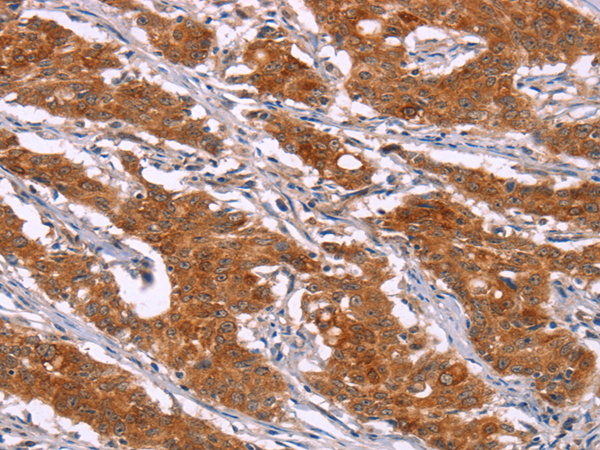

分类: 科研抗体货号: P11835别名: CD50; CDW50; ICAM-R应用: IHC反应种属: Human